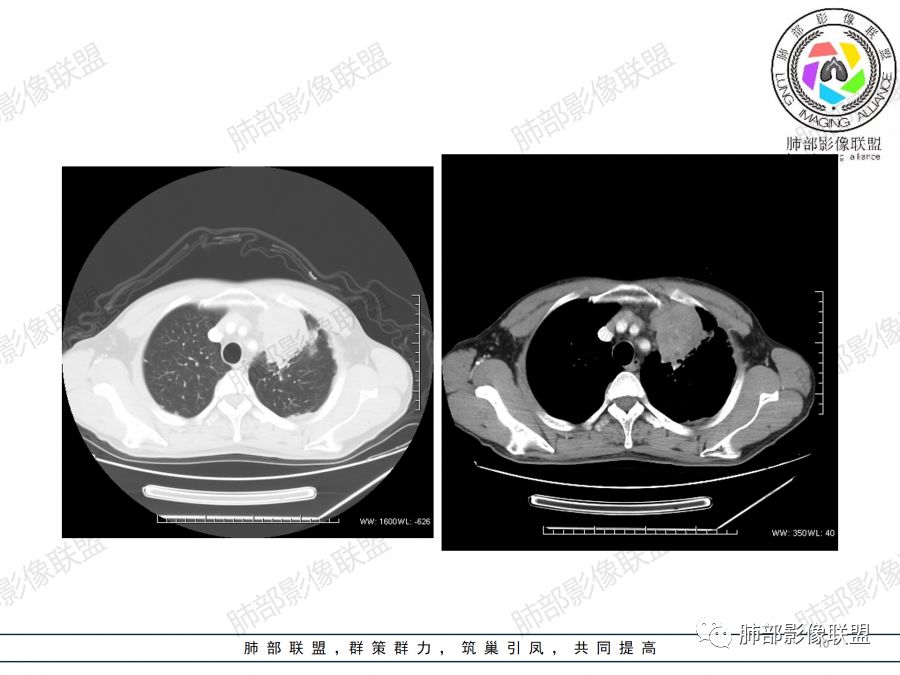

小赵:

首先定位肺内,理由是内乳动脉未见移位。左肺上叶前段肿块,边界清楚,边缘呈分叶状,增强扫描呈不均匀强化,内见边界不清无强化坏死区。同时于病灶内见多发迂曲走形边缘毛糙血管影。考虑恶性,建议穿刺。

王秀仙:

左肺上叶不规则软组织肿块,分叶,病灶内密度不均匀,周围可见磨玻璃影,外侧可见局限性肺气肿,增强后轻度强化,病灶内强化血管增粗且模糊,坏死区无强化,纵隔淋巴结肿大,考虑恶性占位,鳞癌。鉴别结核。

Coke with ice:

男,47岁,咳嗽咳痰一月。病灶位于左内乳动脉内缘,定位肺内,呈团片状异常密度影,整体沿支气管气管束走形分布,由肺门达胸膜下,于近肺门侧病灶形态相对较小,病灶远端相对较大,病灶整体密度偏均匀,强化偏明显,病灶内见多发支气管扩张并粘液栓形成,且扩张支气管粗细不均,直达病灶以远,病灶内血管走形正常、粗细均匀,病灶周围见边缘模糊磨玻璃及少许腺泡结节。左肺门及纵隔略大淋巴结,左侧胸膜局限性增厚。诊断:左肺上叶前段异常密度影,炎性肉芽肿性病变可能,结核不能除外,建议穿刺活检除外恶性肿瘤。

sun dt:

支持肉芽肿性炎,肺癌待排,穿刺活检。